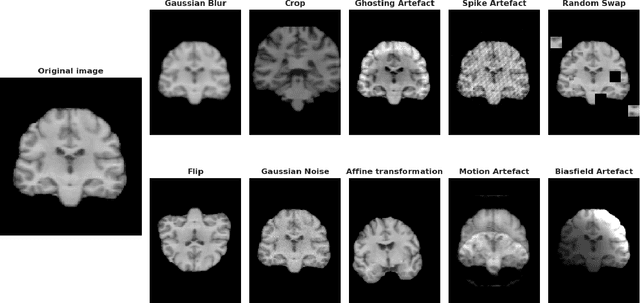

Abstract:Deep Learning (DL) and specifically CNN models have become a de facto method for a wide range of vision tasks, outperforming traditional machine learning (ML) methods. Consequently, they drew a lot of attention in the neuroimaging field in particular for phenotype prediction or computer-aided diagnosis. However, most of the current studies often deal with small single-site cohorts, along with a specific pre-processing pipeline and custom CNN architectures, which make them difficult to compare to. We propose an extensive benchmark of recent state-of-the-art (SOTA) 3D CNN, evaluating also the benefits of data augmentation and deep ensemble learning, on both Voxel-Based Morphometry (VBM) pre-processing and quasi-raw images. Experiments were conducted on a large multi-site 3D brain anatomical MRI data-set comprising N=10k scans on 3 challenging tasks: age prediction, sex classification, and schizophrenia diagnosis. We found that all models provide significantly better predictions with VBM images than quasi-raw data. This finding evolved as the training set approaches 10k samples where quasi-raw data almost reach the performance of VBM. Moreover, we showed that linear models perform comparably with SOTA CNN on VBM data. We also demonstrated that DenseNet and tiny-DenseNet, a lighter version that we proposed, provide a good compromise in terms of performance in all data regime. Therefore, we suggest to employ them as the architectures by default. Critically, we also showed that current CNN are still very biased towards the acquisition site, even when trained with N=10k multi-site images. In this context, VBM pre-processing provides an efficient way to limit this site effect. Surprisingly, we did not find any clear benefit from data augmentation techniques. Finally, we proved that deep ensemble learning is well suited to re-calibrate big CNN models without sacrificing performance.